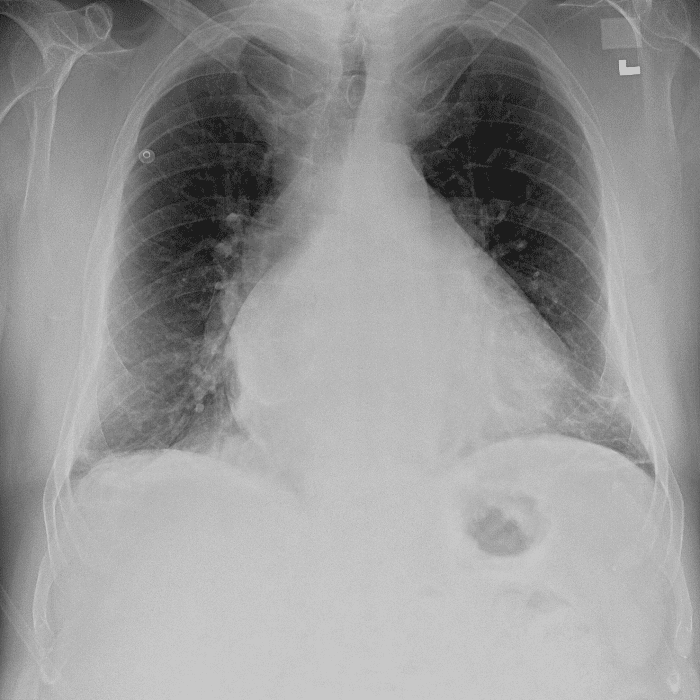

Practice Cases